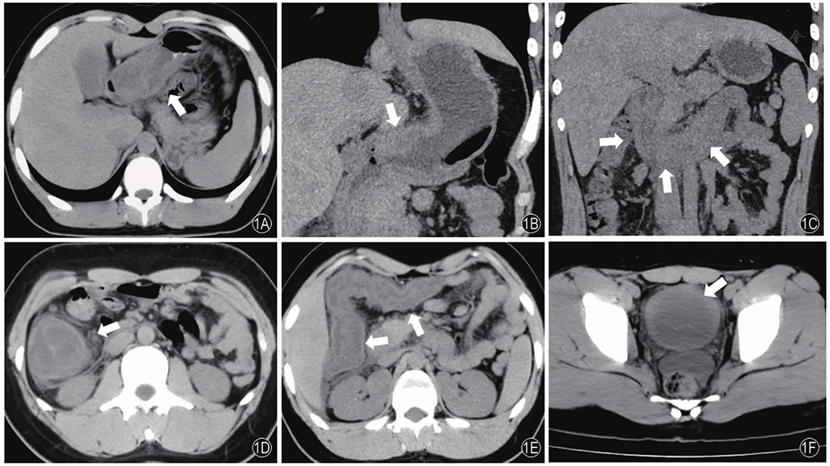

患者男性,15岁,因腹痛伴呕吐10余天,加重1天于2021年7月9日入院。既往"阑尾炎"病史1年余,药物保守治疗。患者于2021年6月21日无明显诱因出现腹痛伴呕吐,腹痛为右侧腹部阵发性绞痛,无其他部位放射,与进食排便无相关,伴频繁恶心、呕吐,非喷射性,呕吐物为所进食物,混有宿食,酸臭明显,伴腹泻,每日排黄色稀水样便6~8次,无鲜血及脓液,于当地诊所按"阑尾炎、胃肠炎"输液治疗数天,症状无好转,逐于2021年7月1日就诊于我院急诊。血液分析:白细胞10.45×109/L(正常值3.5~9.5×109/L),中性粒细胞6×109/L,淋巴细胞2.35×109/L,单核细胞0.71×109/L,嗜碱性粒细胞0.06×109/L,嗜酸性粒细胞计数1.33×109/L(正常值0.02~0.52×109/L),嗜酸性粒细胞百分比12.7%(正常值0.4~8.0%),红细胞计数5.19×109/L,血小板计数305×109/L,血红蛋白141 g/L,C反应蛋白3.05 mg/L,红细胞沉降率2 mm/1 h。生化全项:尿酸472 μmol/L(正常值208~506 μmol/L),余无异常。同日CT检查:胃窦、十二指肠、空肠近段、回肠末段、升结肠及右半横结肠肠壁增厚、水肿,呈分层样表现(图1A~1E),腹腔少量积液,并见膀胱壁弥漫性增厚(图1F)。连续7天予以输注头孢曲松及止痛药等治疗,腹痛稍缓解,仍有间断恶心、呕吐,每日排黄色稍成形便2~3次。1天前患者进食海鲜后出现剧烈腹痛,为持续性钝痛,恶心、呕吐较前频繁,同时出现尿频、尿急等尿路刺激症状,尿液蛋黄色,沫稍多,为求诊治,于2021年7月9日以"腹痛"收入我院消化科。血液分析:白细胞17.58×109/L,其中嗜酸性粒细胞计数6.23×109/L,嗜酸性粒细胞百分比35.4%,中性粒细胞7.82×109/L。生化全项:尿酸533 μmol/L,IgE 1427 IU/mL(正常值1.31~165.3 IU/mL)。尿液及沉渣分析:尿液呈淡黄色,轻度浑浊,尿微量白蛋白0.15 g/L。2021年7月9日CT检查:胃窦、十二指肠大致同前,空肠、回肠、升结肠及横结肠肠壁增厚程度及范围较前进展,腹腔积液较前增多,右侧胸腔新发少量积液;膀胱壁增厚较前进展。2021年7月12日完善骨髓穿刺骨髓像:粒系增生活跃,原粒未见,中、晚粒、杆状核比值偏低,形态未见明显异常,可见33%嗜酸性粒细胞,提示嗜酸性粒细胞增多。2021年7月12日胃肠镜提示:胃窦、十二指肠、空肠近段、回肠末段、升结肠及横结肠黏膜明显肿胀,管腔狭窄,表面散在充血红肿、糜烂(图2)。病理回报:胃窦黏液型黏膜慢性炎(++),活动性(+),少量嗜酸性粒细胞浸润,固有膜纤维组织增生;十二指肠降段,小肠绒毛萎缩,可见潘氏腺,固有层见嗜酸性粒细胞浸润;结肠黏膜组织,固有层较多嗜酸性粒细胞浸润,提示嗜酸细胞性胃肠炎(图3)。膀胱镜及病理结果:镜下膀胱黏膜弥漫性充血、水肿,病理组织学检查示黏膜层见大量嗜酸性粒细胞浸润,并混有少许淋巴细胞、浆细胞。过敏源检测对鸡肉、鸡蛋、蘑菇、小麦、鳕鱼等呈阳性。结合组织学检查诊断为嗜酸细胞性胃肠炎合并膀胱炎。给予泼尼松40 mg,qd,晨起顿服2周,然后每周减5 mg至停药,余继续予以抑酸、补液、调节肠道菌群及营养支持治疗,嘱患者暂避免进食大豆、小麦、蛋、奶、花生、坚果及鱼类等食物。

图1 腹部CT检查结果注:1A、1B胃窦壁明显增厚(↑);1C十二指肠壁明显增厚,周围脂肪间隙模糊(↑);1D降结肠壁明显分层样增厚,周围脂肪间隙模糊(↑);1E结肠肝曲及横结肠明显分层样增厚(↑);1F膀胱壁弥漫性增厚(↑)